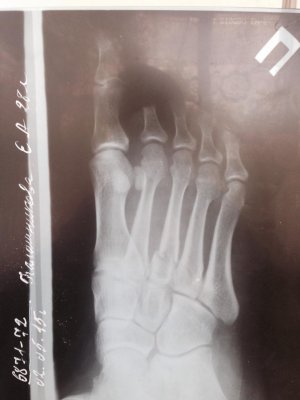

Перелом случился 2.05.2015. Неудачно споткнулась, упала и перелом. В гипсе была до 27.05.2015.на последнем приеме сделали рентген, сняли гипс и сказали рассаживаться и чем больше буду ходить, тем быстрее все заживет.